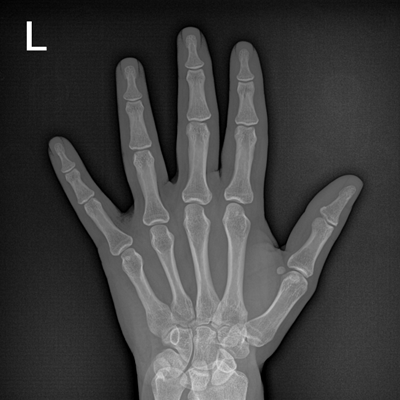

Clinical picture

臨床圖片